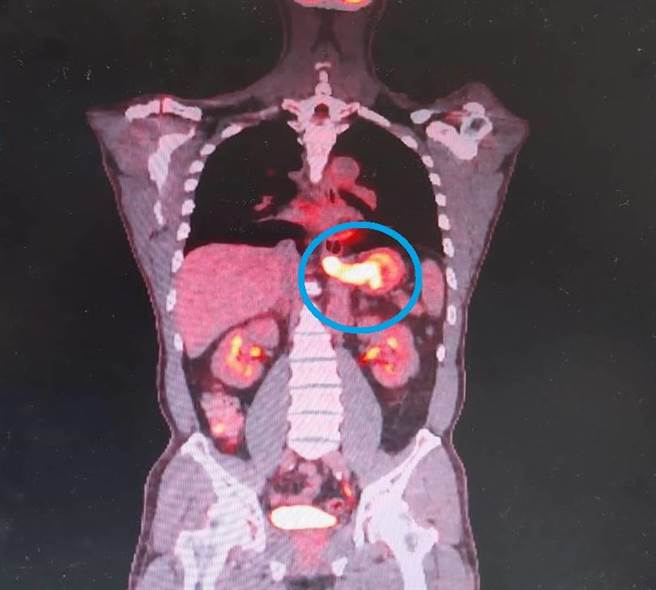

陈先生经正子扫描检查证实为食道癌及胃癌(蓝圈处)。(大千医院提供/李京升苗栗传真)

陈姓男子这两个月期间体重下降近5公斤,因此医师建议安排胃镜检查,结果发现在食道胃接合处和胃贲门部有肿瘤,切片病理报告显示为腺癌,经电脑断层和正子扫描做癌症分期检查,证实为食道癌第3期、胃癌第4期。